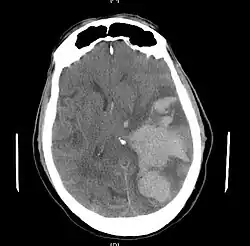

Subfalcine herniation on CT

In cingulate or subfalcine herniation, the most common type, the innermost part of the frontal lobe is scraped under part of the falx cerebri, the dura mater at the top of the head between the two hemispheres of the brain.[8][13] Cingulate herniation can be caused when one hemisphere swells and pushes the cingulate gyrus by the falx cerebri.[7] This does not put as much pressure on the brainstem as the other types of herniation, but it may interfere with blood vessels in the frontal lobes that are close to the site of injury (anterior cerebral artery), or it may progress to central herniation.[8] Interference with the blood supply can cause dangerous increases in ICP that can lead to more dangerous forms of herniation.[14] Symptoms for cingulate herniation are not well defined.[14] Usually occurring in addition to uncal herniation, cingulate herniation may present with abnormal posturing and coma.[7] Cingulate herniation is frequently believed to be a precursor to other types of herniation.[14]